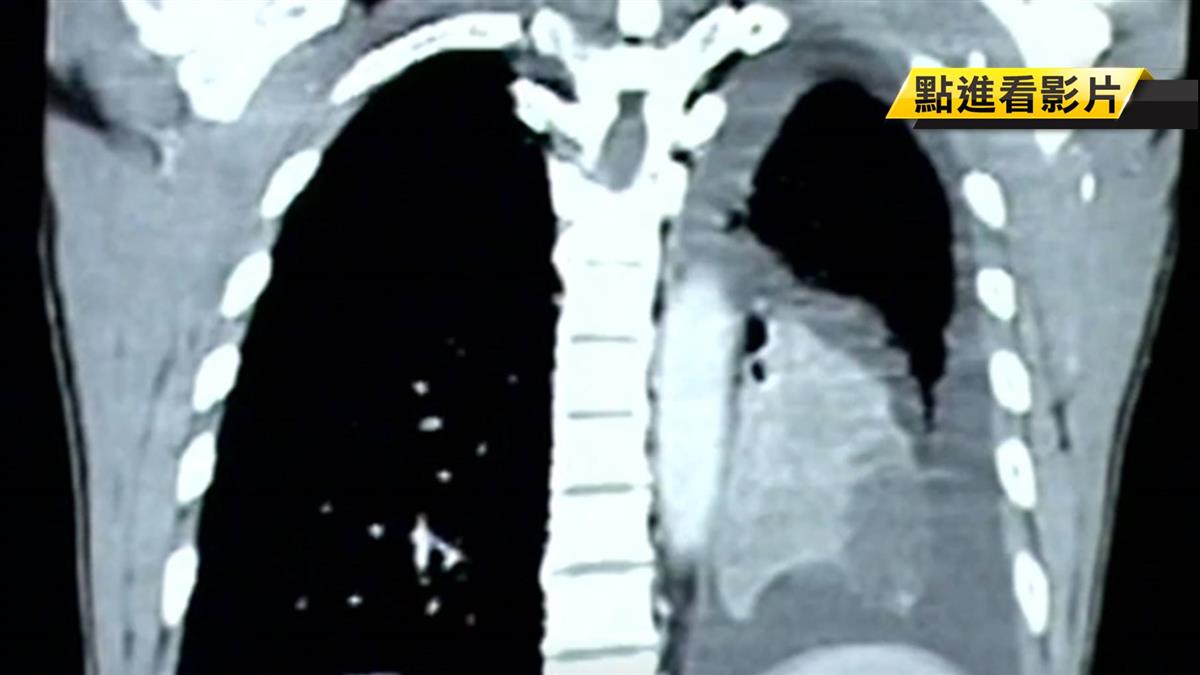

肺纖維化講白話一點,就是肺部組織受傷後結痂,阻礙肺部換氣功能,原本柔軟的肺泡變得沒彈性,氧氣進不來,再加上肺泡交換氧氣的能力也下降,所以呼吸會變得比較不順暢。

台大兒童醫院小兒部醫師李秉穎:「破壞我們的肺泡,肺臟組織沒有辦法作,換氣功能的話,我們的組織修復,就是會用纖維組織,來取代原來被破壞掉的肺泡,那就是所謂的肺部纖維化。」

▼肺纖維化的症狀。(圖/東森新聞)